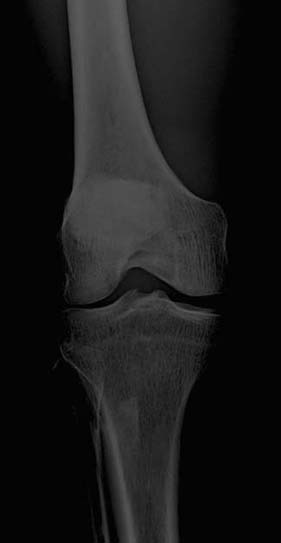

A radiographic image must have sufficient brightness to visualize the anatomic structures of interest (Fig. 3-13). A radiographic image that is too light has too much brightness to visualize the structures of the anatomic part (Fig. 3-14). Conversely, a radiographic image that is too dark has insufficient brightness, and the anatomic part cannot be well visualized (Fig. 3-15).The radiographer must evaluate the overall brightness in the image to determine whether it is sufficient to visualize the anatomic area of interest. He or she then decides whether the radiographic image is diagnostic or unacceptable.

FIG. 3-14 Brightness. Radiographic image with excessive brightness. Brightness altered with postprocessing. (From Johnston JN, Fauber TL: Essentials of Radiographic Physics and Imaging, ed 3, St. Louis, 2020, Mosby.)

FIG. 3-15 Brightness. Radiographic image with insufficient brightness. Brightness altered with postprocessing. (From Johnston JN, Fauber TL: Essentials of Radiographic Physics and Imaging, ed 3, St. Louis, 2020, Mosby.)